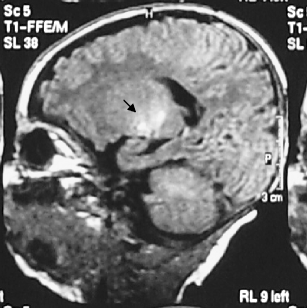

Fig. 1